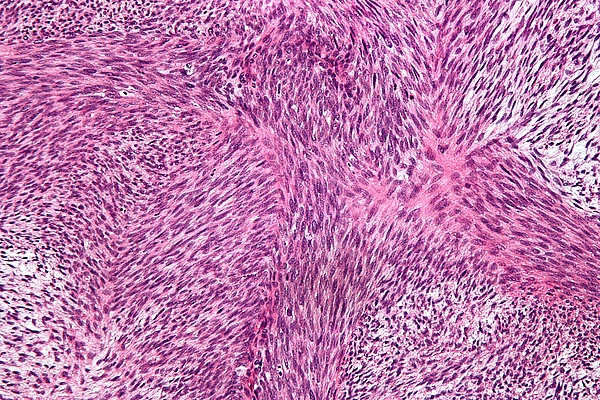

В одних случаях фибросаркома отграничена, имеет вид узла, в других — границы её стерты, опухоль инфильтрирует мягкие ткани. Состоит из незрелых фибробластоподобных клеток и коллагеновых волокон. В зависимости от степени зрелости и взаимоотношения клеточных и волокнистых элементов опухоли различают дифференцированную и низкодифференцированную фибросаркому. Дифференцированная фибросаркома имеет клеточно-волокнистое строение, причем волокнистый компонент преобладает над клеточным. Низкодифференцированная фибросаркома состоит из незрелых полиморфных клеток с обилием митозов, которая обладает более выраженной злокачественностью и чаще даёт метастазы. Саркомы из круглых или полиморфных клеток могут иметь невыясненный гистогенез, тогда говорят о неклассифицируемой опухоли.